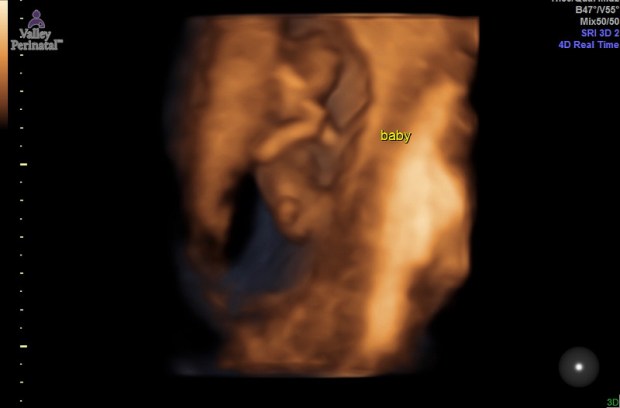

During our 12 week ultrasound the baby was very active! As soon as the ultrasound tech put the wand on my stomach, we could see the baby spinning and flipping around. We tried to get some close photos of baby’s face, but baby kept hiding behind his/her arms. We did, however, get a perfect profile picture of Baby Sells and I fell in love. I can’t wait to feel baby’s first move! We also got lucky at our 14 week checkup with an unexpected ultrasound! My doctor was training a new staff member and had her sit in on our appointment. She explained that 14 weeks is one of the best times to see a baby because of the development and space that there still is in the womb. She asked if I would be okay having an ultrasound done to show her. Uh yes, any chance we have to see our baby we’d take it! We walked into the ultrasound room and got ready to see our baby. Right away we saw baby stretched all the way out rolling around and waving his/her arms. Our doctor kept mentioning how long the baby’s legs were. The baby kept doing jump squats. I have a feeling once I can start feeling him/her, it’s going to be nonstop! Then, we saw the baby opening and closing it’s mouth. Our doctor said it was the baby drinking the amniotic fluid. It looked like like a little pac man. My heart just melted.

Baby Sells at 12 weeks.

Hi Baby!